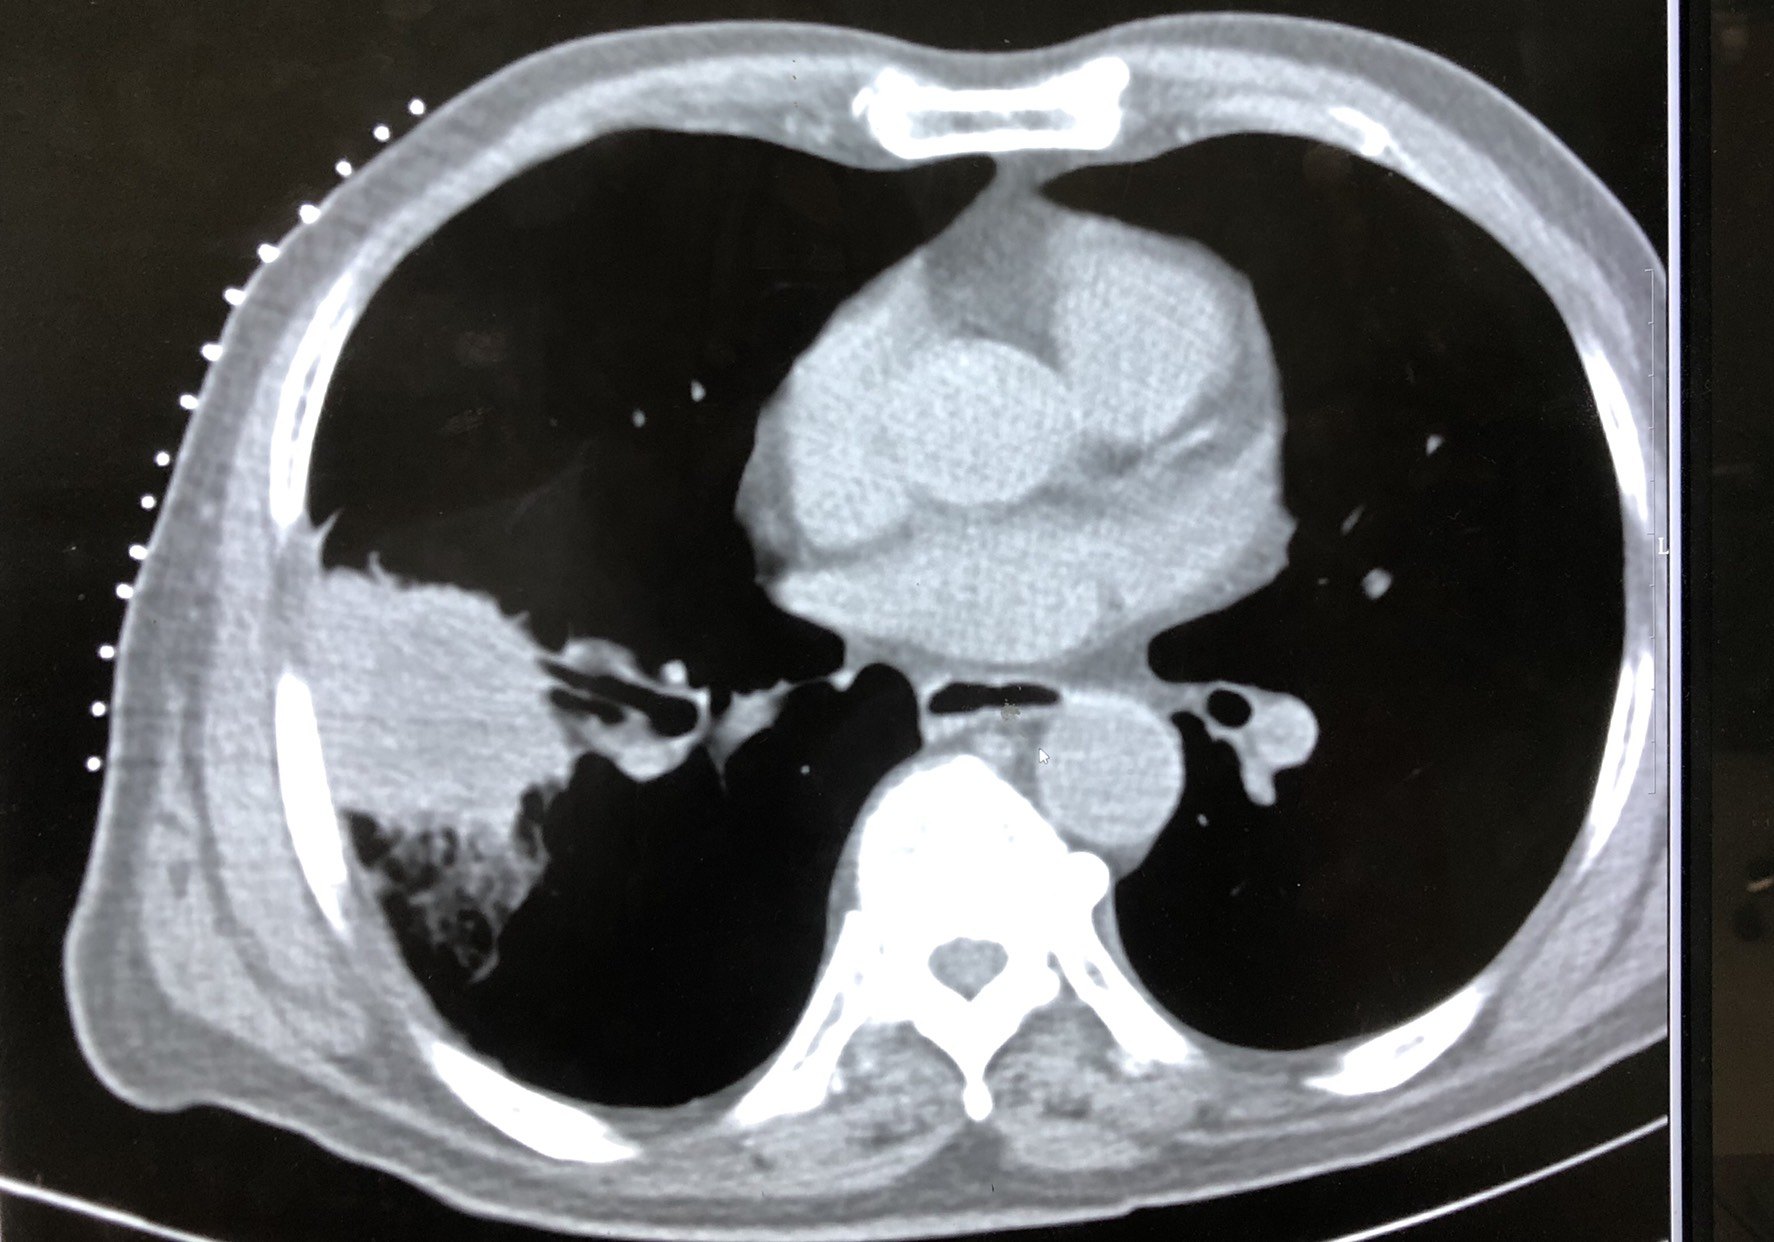

图5氩氦刀后七个月,肿瘤进展。

点评:肺肿瘤的消融治疗做到有效不难,但是要达到局部根治的目的却不容易。肺肿瘤的治疗和肝癌的消融治疗比较更加需要强调和化疗靶向治疗及免疫治疗等多种技术的配合才能获得更加好的效果。